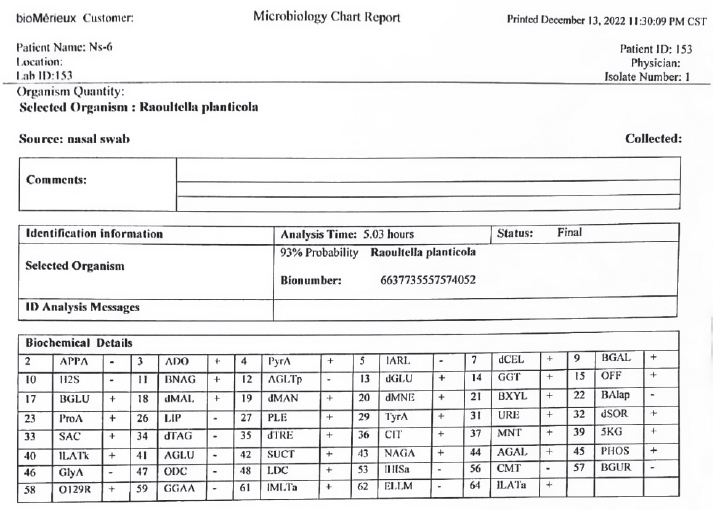

AbstractBackground: The bacteriological and histopathological study of Raoultella planticola in local rabbits is not presented in previous research. There is no specific information about studying this bacterium in local rabbits. Hypothesis: The present study was based on bacteriological and histopathological changes in the trachea and lungs of local rabbits, as the samples were collected from 50 unhealthy local rabbits that appeared to be suffering from respiratory signs. Aims: To study the bacteria that were isolated for the first time from sheep suffering from respiratory infections, and diagnose them through VITEk2. Methods: We injected the isolated bacteria into (50) group of local rabbits (Oryctolagus cuniculus) and studied the histopathological changes in the trachea and lungs. Due to their similar morphological characteristics, our investigation reported this bacterium as Gram-negative rods. Then used the VITEK2 system to confirm the species of bacteria (93% Probability). Results: The animals clinically showed results (dullness with nasal and ocular discharge and cough). Then, euthanasia was performed to sacrifice animals seven days post-infection. The trachea and lungs were used in a histopathological study using routine Hematoxylin and Eosin stained. In this study, emphysema and bronchitis are often grouped under the heading of chronic obstructive pulmonary disease (COPD). Conclusion: Raoultella planticola infections are uncertain, and further studies are required. The previous difficulties in the identification of R. planticola may be explained by the introduction of more detailed identification techniques, which are explained in the present study. The conclusion of this study also provides that Raoultella planticola causes mild to moderate emphysema in local rabbits. Keywords: Respiratory system, Oryctolagus cuniculus, Raoultella planticola, Parenchyma, Alveoli. IntroductionRaoultella planticola is a Gram-negative, non-motile, aerobic, encapsulated bacterium belonging to the Enterobacteriaceae family (Chun et al., 2014). In Iraq, local rabbits have a second small pair of upper incisors (Harcourt-Brown, 2002). The rabbits among the laboratory animals have been used as an experimental model for research (Ghoshal and Bal, 1989). It belongs to the genus Raoultella under the Enterobacteriaceae family. Two species are clinically important (Sahu et al., 2020). The microbiological identification of R. planticola remains a challenge even after 30 years of its identification (Howell and Fakhoury, 2017). The gastrointestinal tract and the upper respiratory tract are the typical reservoirs of R. planticola (Sękowska, 2017). Infections related to rare pathogens are very challenging to treat due to a lack of enough data in the medical literature (Sahu et al., 2020). These strains can act as a reservoir for these resistance genes (Demiray, et al., 2017). The lung is a soft, compact, and spongy mass of tissues lying in the pleural cavity within the thorax. Each lung is covered by a fold of coelomic epithelium formed of two layers, a layer which in contact with the organ (visceral pleura) and that lines the chest wall (parietal pleura). Between these two layers of pleura, there is a pleural space, which is a potential space containing a small amount of fluid. Each lung is divided into lobes (Ramchandi et al., 2001). Klebsiella pneumoniae is a type of gram-negative bacteria that is normally found in the human intestines without causing any disease. However, if it enters other systems of the body, it can cause different types of healthcare-associated infections, including pneumonia, bloodstream infections, wound or surgical site infections, and meningitis (Centers for Disease Control and Prevention 2010). This research aims to study the Raoultella planticola that were isolated for the first time from respiratory infections, then confirmation by the VITEK2 system, and study the morphological characteristic. Materials and MethodsSamples were collected from 50 animals that appeared suffering from respiratory signs, and in the laboratory used routine steps to the identification of bacteria culturing, gram stain, and urease test. After that, the VITEK2 system was used to confirmed the species of Raoultella planticola, VITEK2 system has two test depending on the kit that we used. The first is a test of the biochemical reaction of bacteria with a chemical substance, and the second is a test of the resistance of bacteria to antibiotics. The antibiotics profile will be mentioned later. After that, the isolated bacteria were diluted and injected into 5 local rabbits regardless of sex in the Miles and Misra method to get the minimal dose that can cause infection (5 animals used for control) in the current study. The rabbits were scarified under good health conditions and followed the appropriate instructions of the animal ethics of the University of Baghdad College of Veterinary Medicine in Iraq. Finally collected specimens for the histology study of the respiratory system, the trachea, bronchus, and lungs. Histopathological aspect of the studyThe first step after samples collection is fixation by formaldehyde 10% then dyhydration via ethanol (70%, 80%, 90%, and 100%) for 2 hrs each of step. After that xylen was used as a clearing agent for 2 hrs. Then the samples were impregnated in melted paraffin wax (55°C–58°C) for 2hrs. Each piece of sample was embedded in paraffin wax and finally cut into sections (5–6 µm thickness) by using the rotary microtome (Microtome Bright 5030). The sections were stained with haematoxylin and eosin for routine histology (Suvarna et al., 2019). All stained slides were examined under the light microscope and photographed with a digital camera (USB) connected to the computer, camera should adjusted, and setliy should be fixed throughout all steps of capturing with different magnification powers. The slides were captured directly from computer at various adjustment powers (x10, x40, x100, and x400) to evaluate the histopathological features. The examination and photograph were conducted at histopathology and microbiological Lab. College of Medicine/University of Fallujah. The histopathological and staining techniques that used were as following, Harris Hematoxylin and Eosin stain (H&E): This stain was used to detect the general features of the tissue (Luna, 1968; Suvarna et al., 2013). Ethical approvalThis study was conducted in conformity with the rules of the Animal Ethics Committee of the Faculty of Veterinary Medicine at the University of Kufa (license number: 27735 in 13/12/2022). ResultsBacteriological studyTo study the pathogenesis of Raoultella planticola through its natural route of infection (nasal route), an experimental infection was conducted using a dose of 159,000 CFU/mL. Ten healthy rabbits were divided into two subgroups: a control group (5 healthy animals) and an infected group (5 healthy animals inoculated intranasally with Raoultella planticola at a dilution of 10−3. The infected animals exhibited clinical signs, including dullness, nasal discharge, and ocular discharge. After seven days post-infection, the rabbits were euthanized, and post-mortem examination revealed pulmonary emphysema at the mentioned dose. Bacteriological analysis confirmed Raoultella planticola as Gram-negative rods. The VITEK2 system identified the species with a 93% probability, and 23 samples were positive. The isolates Raoultella planticola were then injected into local rabbits (regardless of sex) after dilution using the Miles and Misra method to determine the minimal infective dose (intranasal 10−3, 2.5 ml instillations). Antimicrobial susceptibility testingDisk diffusion susceptibility testing was performed following Bernal and Guzmán (1984) and Clinical and Laboratory Standards Institute (CLSI, 2023) guidelines. Fourteen antimicrobial agents were tested against Raoultella planticola: • Amikacin • Amoxicillin/Clavulanic acid • Cefixime • Ceftriaxone • Chloramphenicol • Ciprofloxacin • Gentamicin • Imipenem • Meropenem • Nitrofurantoin • Piperacillin • Streptomycin • Tetracycline • Trimethoprim The average inhibition zone diameters were recorded, and results were interpreted according to CLSI standards (Table 2). Table 2. VITEK2 result show susceptibility of Raoultella planticola.

Fig. 2. A Comparison between Colonies of klebsiella pneumonia (A) culturing on MacConkey agar which appear as mucoid dark pink colony and Colonies of Raoultella planticola (B ) culturing on MacConkey agar appear as mucoid pink colonies Table 1. VITEK2 result show presence of Raoultella planticola.

The Vitek2 system provided reliable identification (93% probability), supporting the accuracy of the isolates used in this study. The antimicrobial susceptibility profile revealed varying resistance patterns, which may have clinical implications for treatment strategies. Further studies are needed to explore the virulence mechanisms and potential zoonotic risks associated with Raoultella planticola. Histopathological resultsHistological examination of lung tissue revealed emphysema and atelectasis (Fig. 6A and B). Emphysema was characterized by permanent enlargement of air spaces distal to the terminal bronchioles, accompanied by destruction of alveolar walls without significant fibrosis.